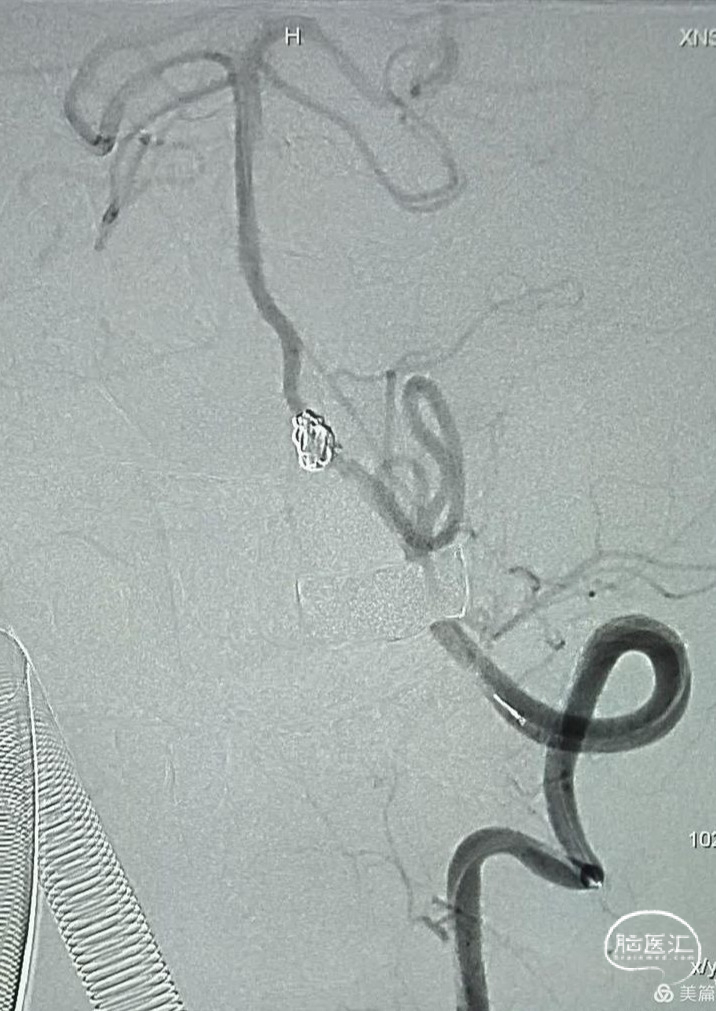

手术方案一旦形成,操作就变得非常简单,微导丝携带微导管很快到达动脉瘤腔。

选择合适的弹簧圈填塞动脉瘤腔,调控微导管的张力,让弹簧圈分布尽量均匀一些。

两枚弹簧圈填塞后造影,见载瘤动脉仍通畅,这种情况仍然有复发并再出血的风险。

继续填塞弹簧圈,瘤体近端约2mm的血管一并栓塞做成“塞子”。

数枚弹簧圈进去,载瘤动脉及动脉瘤致密栓塞,小脑后下动脉显影良好,且有侧支与基底动脉近端联通。